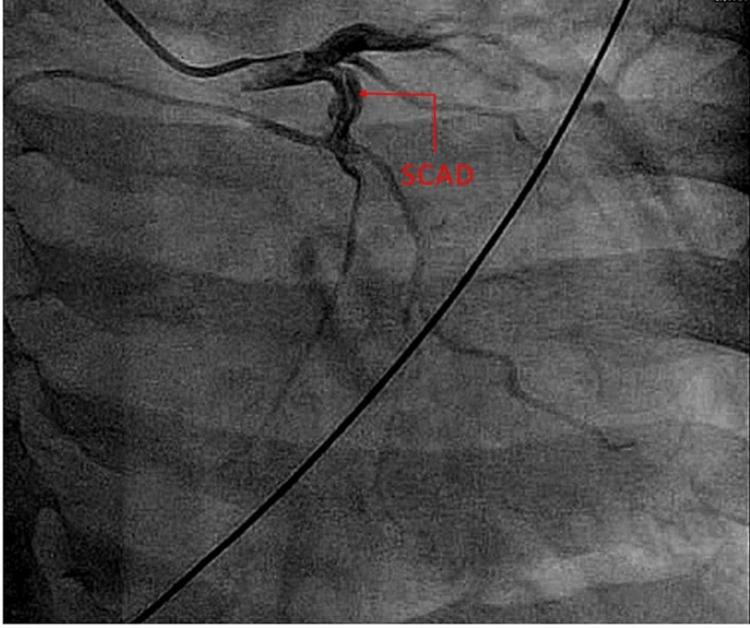

Her vitals were within the normal limits and physical examination revealed decreased chest wall expansion, coarse rhonchi, and prolonged respiratory phase. Laboratory findings were significant for troponin I of 0.64 ng/ml x1 (peaked to 1.87 ng/mL x2, 4.65 ng/ml x3). Urine toxicology was positive for tetrahydrocannabinol (THC). Electrocardiography (ECG), chest X-ray (CXR), and transthoracic echocardiogram (TTE) were unremarkable. Coronary angiography revealed evidence of spontaneous coronary artery dissection in the proximal left circumflex (LCX) artery with Thrombolysis in Myocardial Infarction (TIMI) grade III flow, as shown below in Figure 1 and Video 1.